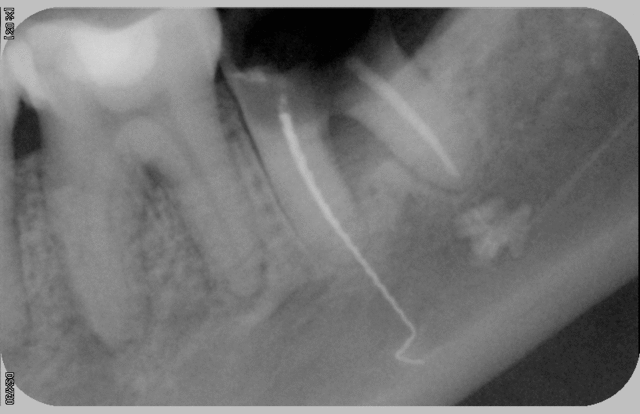

Nouveau système de transfixation par un lentulo, à breveter…

Pas mal du tout le lentulo! (il manque le col du lentulo qund meme.... lol)

Le lentulo, même en faisant exprès je sai pas si j'arriverai à faire mieux...;)combien d'année d'experience de TR lentulo et pâte pour arriver à ce niveau?? lol

> Nouveau système de transfixation par un lentulo, à

> breveter…

rassures moi tu la ressorti ce lentulo?

Il est sorti sans trop de problème et la patiente l'a conservé pour avoir une discussion avec son ancien CD…

si la cortical externe de la mandibule avait été moin dur il serai ressorti par la peau... :)

impressionant la rx que tu nous as postée.

Quels symptomes présentaient le patient? comment l'as tu géré?

la patiente ne présentait aucun symptôme lié aussi bien au dépassement de l'instrument qu'à la pâte

extraction par un collègue spécialisé en Chirurgie buccale

tout est venu d'un seul tenant